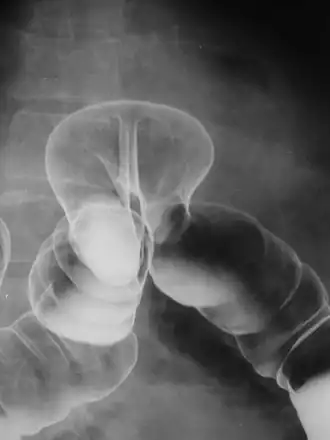

By far the most common hernias (up to 75% of all abdominal hernias) are inguinal hernias, which are further divided into the more common indirect inguinal hernia (2/3, depicted here), in which the inguinal canal is entered via a congenital weakness at its entrance (the internal inguinal ring), and the direct inguinal hernia type (1/3), where the hernia contents push through a weak spot in the back wall of the inguinal canal. An indirect inguinal hernia and a direct inguinal hernia can be distinguished by their positioning in relation to the inferior epigastric vessels. An indirect hernia is situated laterally to these vessels, whereas a direct hernia is positioned medially to them. Inguinal hernias are the most common type of hernia in both men and women. In some selected cases, they may require surgery.

There are special cases where a direct and indirect hernia appear together. A pantaloon hernia (or saddlebag hernia) is a combined direct and indirect hernia when the hernial sac protrudes on either side of the inferior epigastric vessels.